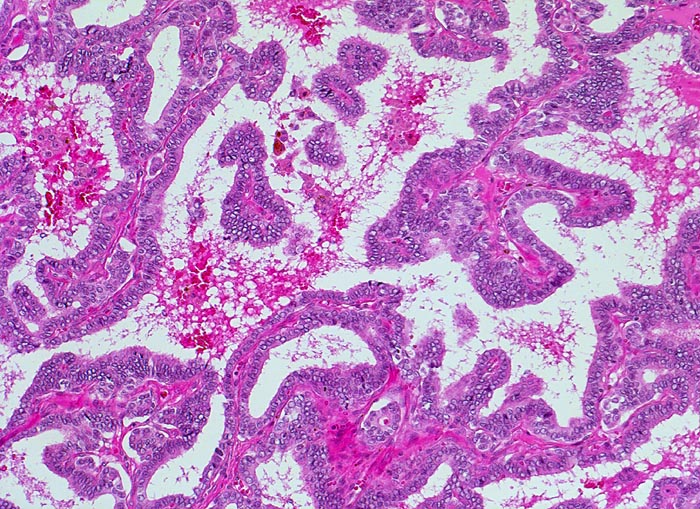

PathoPic ID 4736 - papilläres Schilddrüsenkarzinom

papilläres Schilddrüsenkarzinom

maligner Tumor

Schilddrüse

Endokrinium

Papillärer Tumor.

In der Feinnadelpunktion eines 2cm grossen kalten Knotens werden Karzinomzellen nachgewiesen vereinbar mit einem papillären Schilddrüsenkarzinom.

Histologie

100